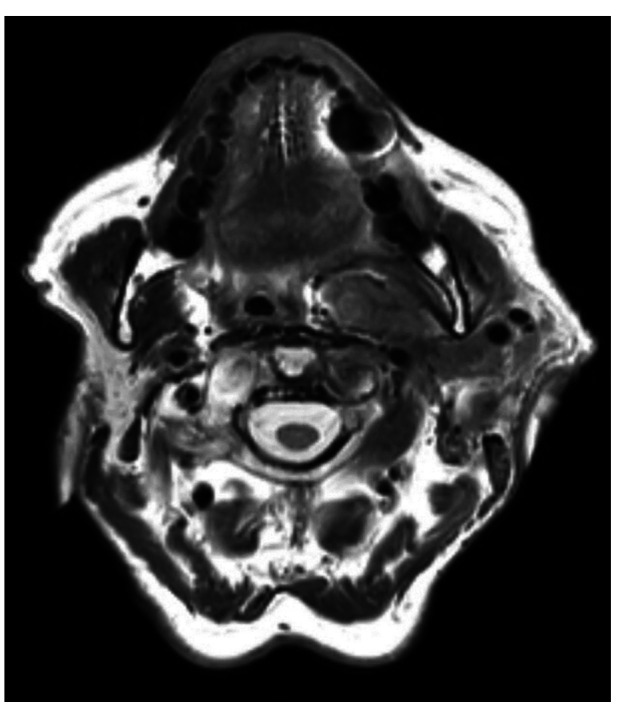

Radiotherapy Treatment of Warthin's Tumor (Cystadenolymphoma).

Warthin肿瘤(囊腺淋巴瘤)的放射治疗。